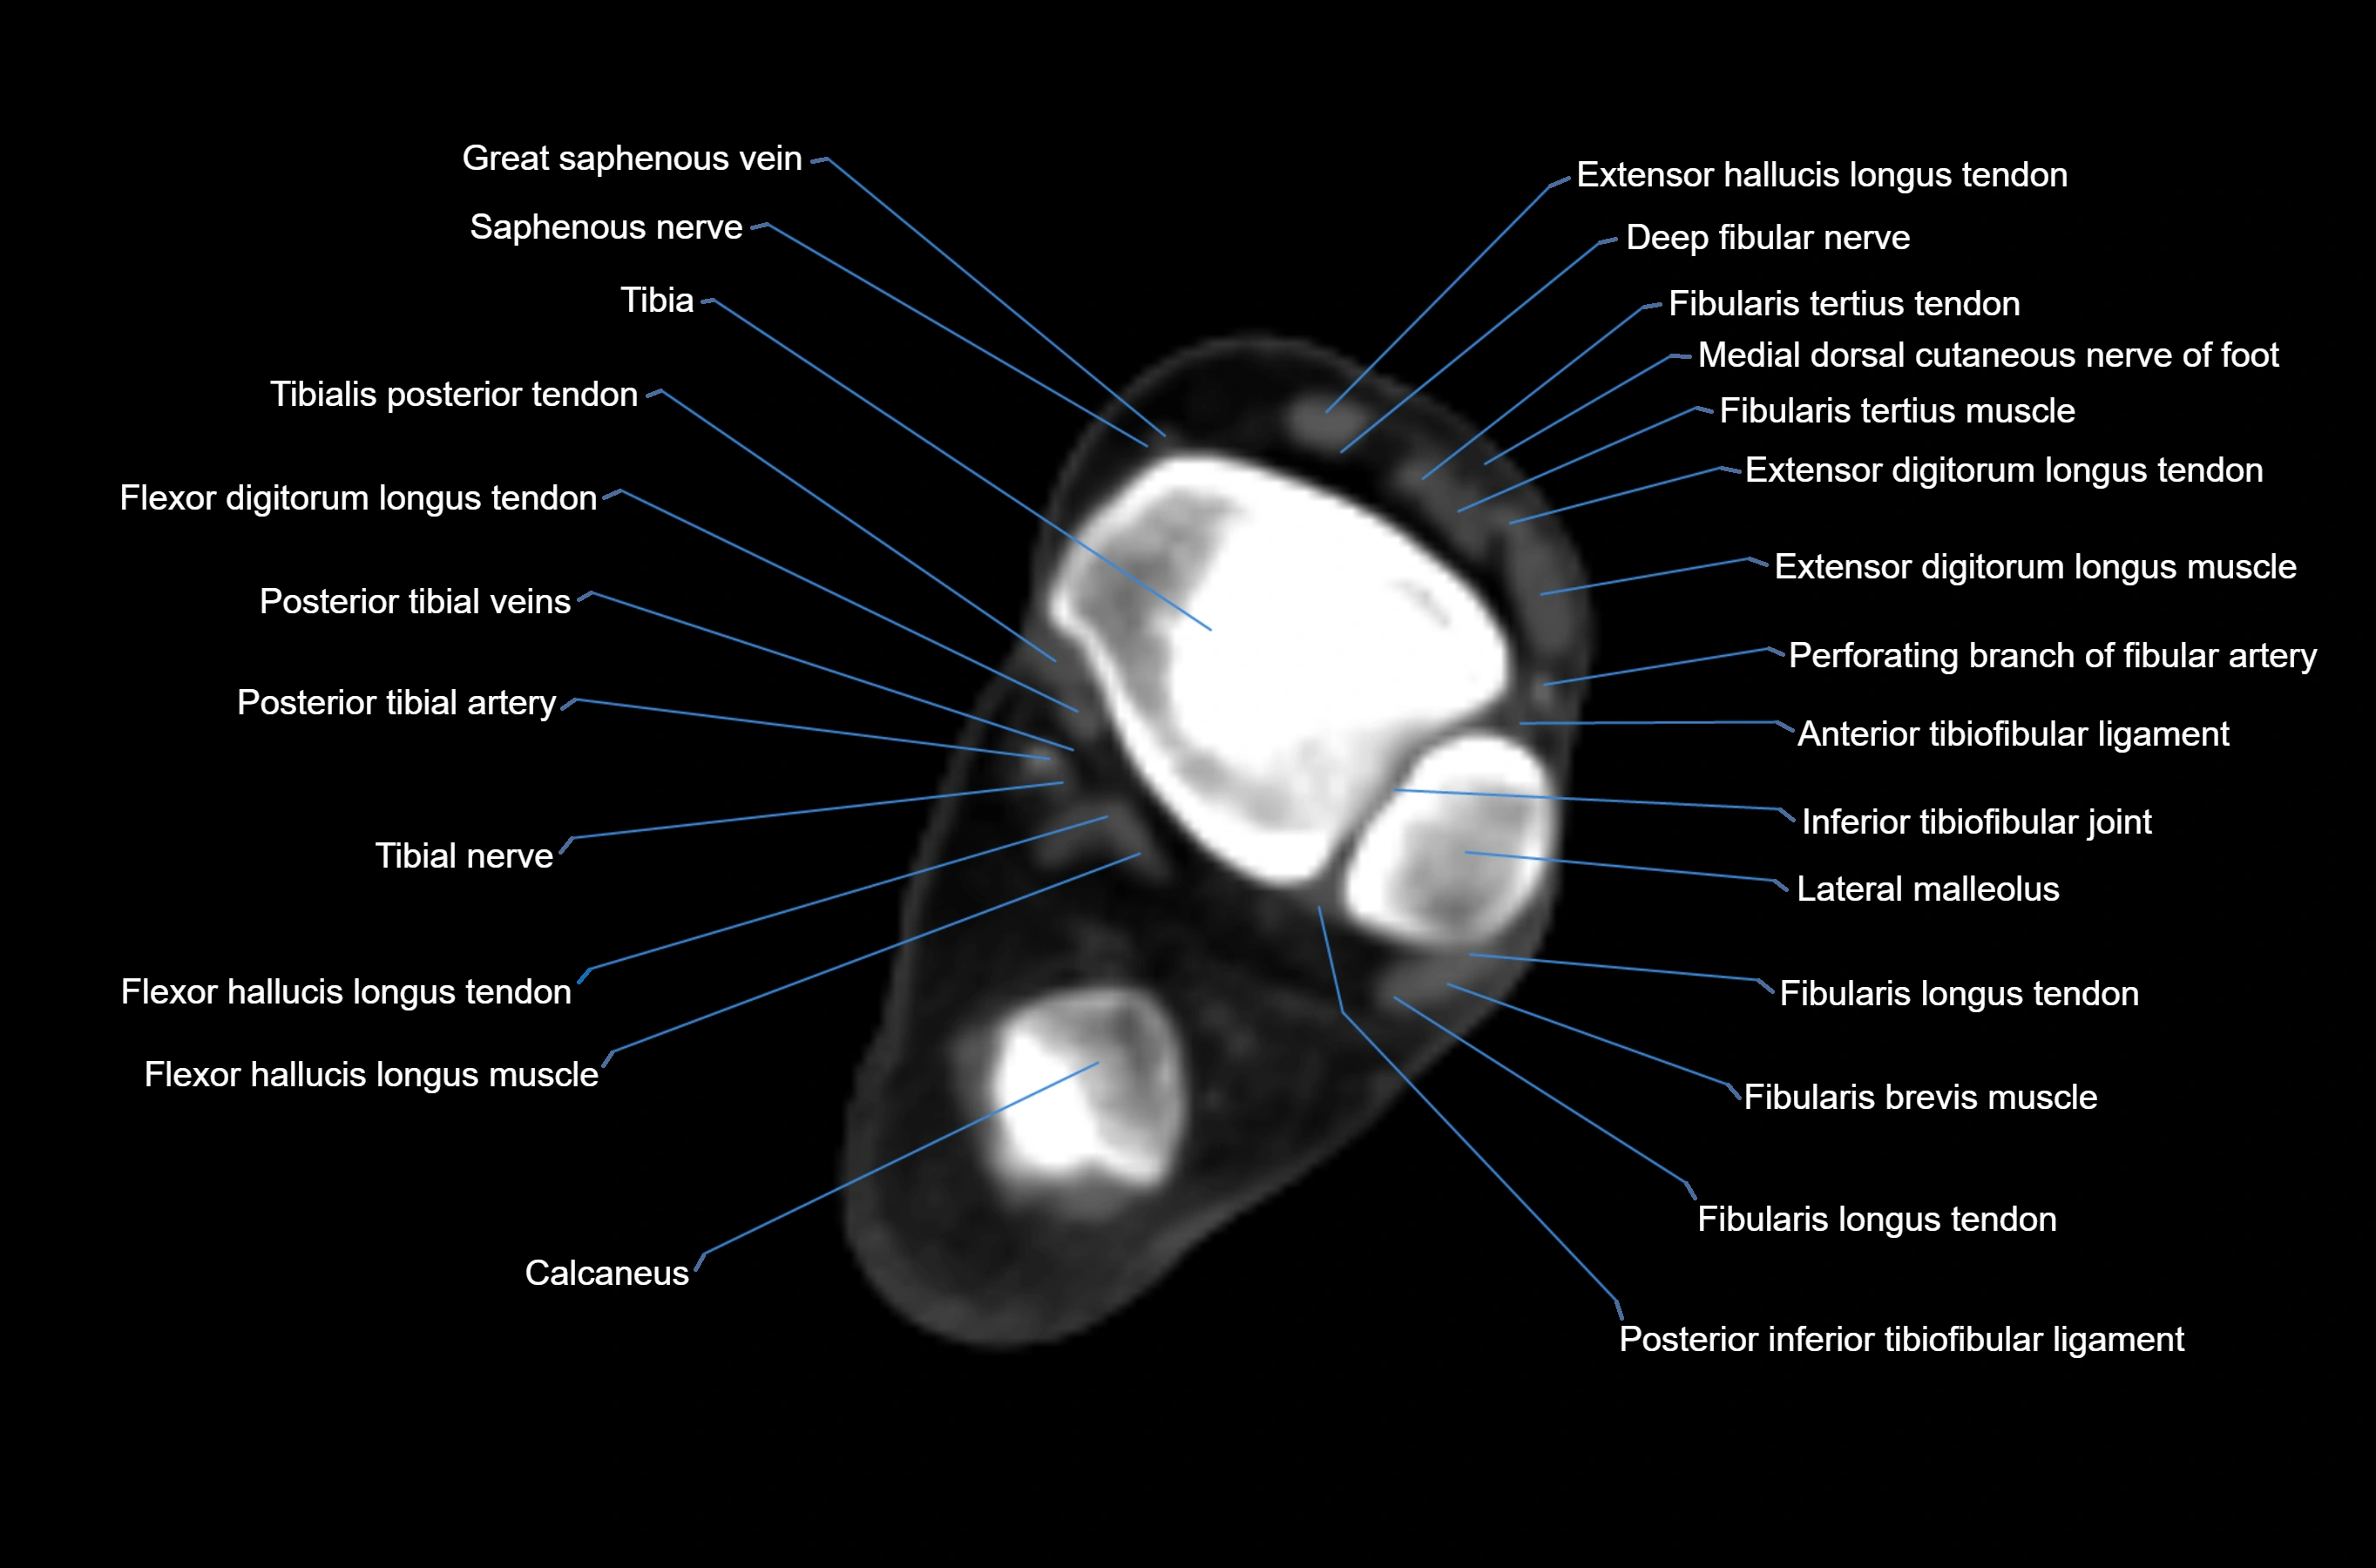

MRI image